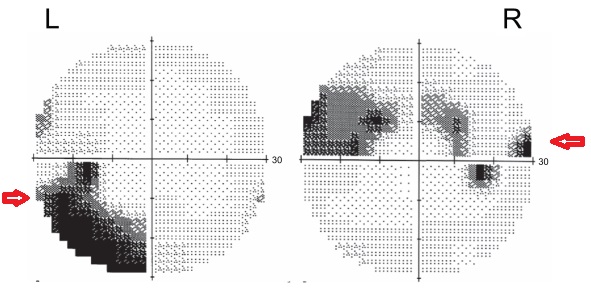

귀쪽 시야결손 Temporal visual field defect

녹내장에서 전형적으로 보이는 시야 손상의 형태는,

앞서이야기한 형태대로,

상부시야에서 활모양암점이 생기기 시작하면서 점점 심해지고,

하부 시야에서도 활모양 암점이 생기기 시작하면서,

결국 고리모양으로 암점이 생기게됩니다.

이러한 암점들은 대부분 중심시야 부근, 즉 맹점의 코쪽시야에서 나타나게되는 소견들입니다.

다른말로 하면, 맹점의 귀쪽시야는 대부분 마지막까지 유지되는 양상을 보이는데,

녹내장이 꽤 진행된 상태에서는 이러한 맹점의 귀쪽시야에서도 결손이 생깁니다.

이를 Temporal Sector Defect 라고합니다.

이는 시신경 유두의 코쪽 RNFL 이 손상이 되면서

이가 담당하는 맹점의 귀쪽 시야에서 암점이 나타나는 것입니다.

Temporal Sector defect 는 진행된 녹내장임을 알려주는 지표입니다.

중심섬(central island)

마지막으로 중심섬은, 앞서 말한 고리모양의 암점이 나타나고,

Temporal Sector defect 까지 나타낙되면서

최종적으로 중심시야 근처에서만 시야가 남은 상태를 의미합니다.

말기 녹내장에서 보이게되는 터널시야(Tunnel vision)의 형태이며,

시야의섬이 모두 가라앉아서 정가운데에 중심시야부분만이 남은 형태라고 하여

중심섬이라고 합니다.